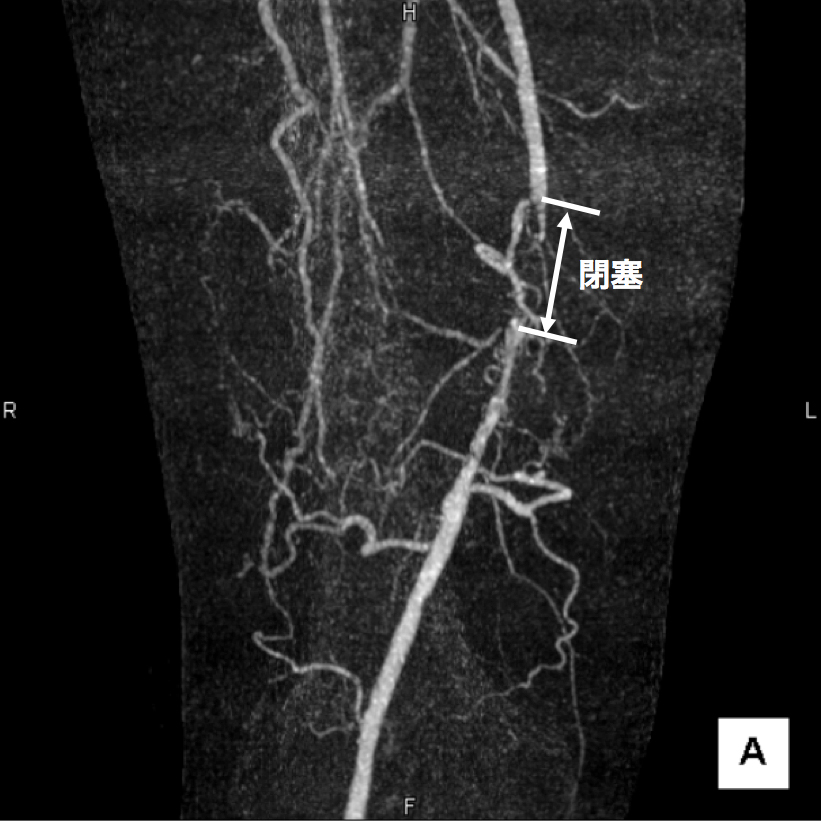

3、造影CT検査 造影剤を点滴しながらCTを撮像することで、血液の流れ、血管の状態などを把握します。情報量が多く治療方針を決定する場合に役立つので当院では特に力を入れている検査です。(図2、3、4)

【図4】下肢造影CT検査 サブトラクションという画像の処理を行うと、血流が途絶えており、血管が完全に閉塞していることがわかります。